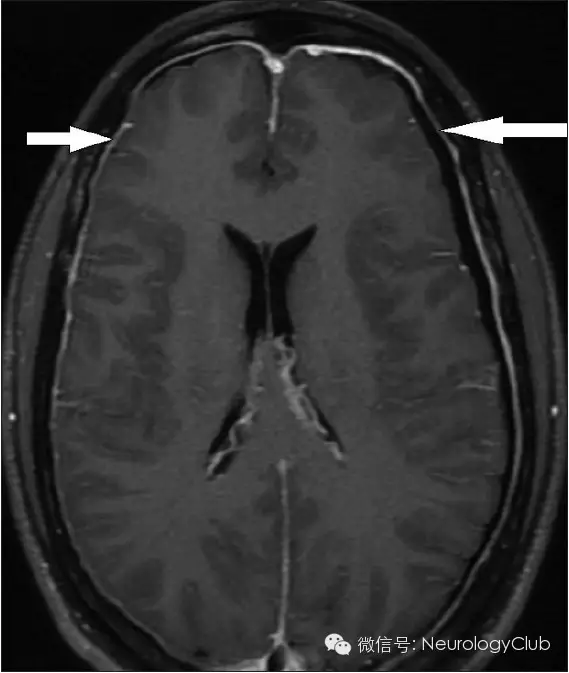

(2)硬脑膜强化(Enhancement of the pachymeninges)

增强扫描时硬脑膜弥漫性增强增厚是颅内低压综合征的最具特征性表现,也是阳性率最高、出现最早的MRI表现。呈不间断的线样增强,无局限性结节,同时经常伴有硬脑膜增厚和皮层静脉的扩张,但从不累及软脑膜。